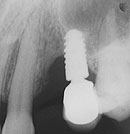

![]() ▲大きく骨吸収してスレッドの露出したチタン系インプラント |

それでもAQBの2ピースなら再結晶化HApコーティングであるため、増骨した骨はかなり残る確率は高いと思うが、チタン系の2ピースでは大幅な増骨をした症例の骨は徐々に吸収する傾向があるという。長年その第一線で活躍してきたチタン系のインプラントロジストの中にも、ここ十数年の経過から、やはり既存骨を重要視して治療を行うことが、リスクを減らし効果を生かす上で欠かせない条件であるという反省が出てきているようである。原則として既存骨の中にインプラント被覆部を収め、対合歯とできるだけ好ましい対向関係で植 立しようという発想の1ピースAQBは、20年前に動き始めたプロジェクトで誕生したインプラントではあるが、きわめて先見の明があったといわざるを得ない。